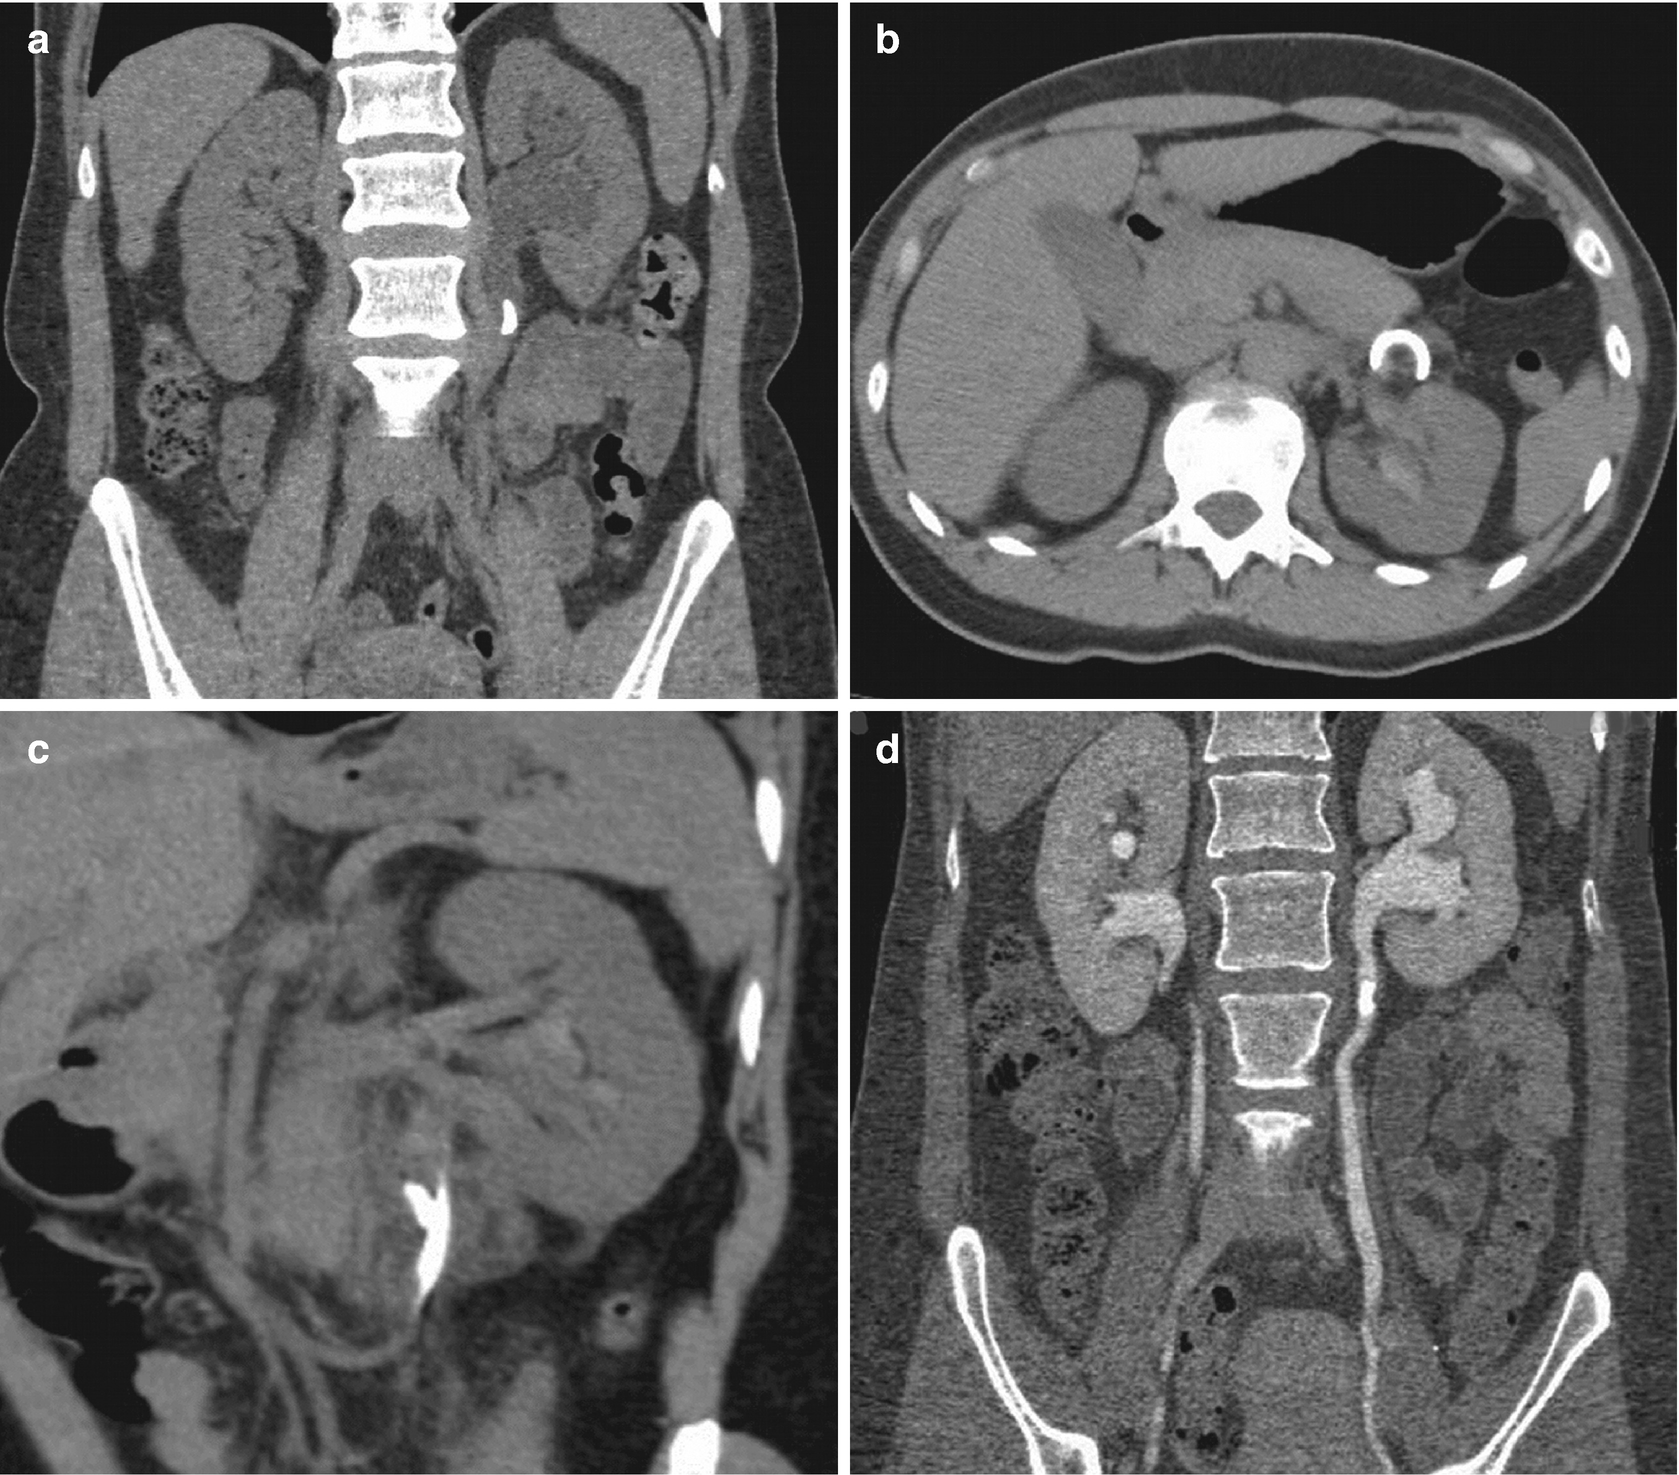

Perioperative Images A Ct Showing Bilateral Nephrolithiasis Three Download Scientific Diagram

A Coronal Demonstration Of Bilateral 8 Mm Nephrolithiasis On Download Scientific Diagram